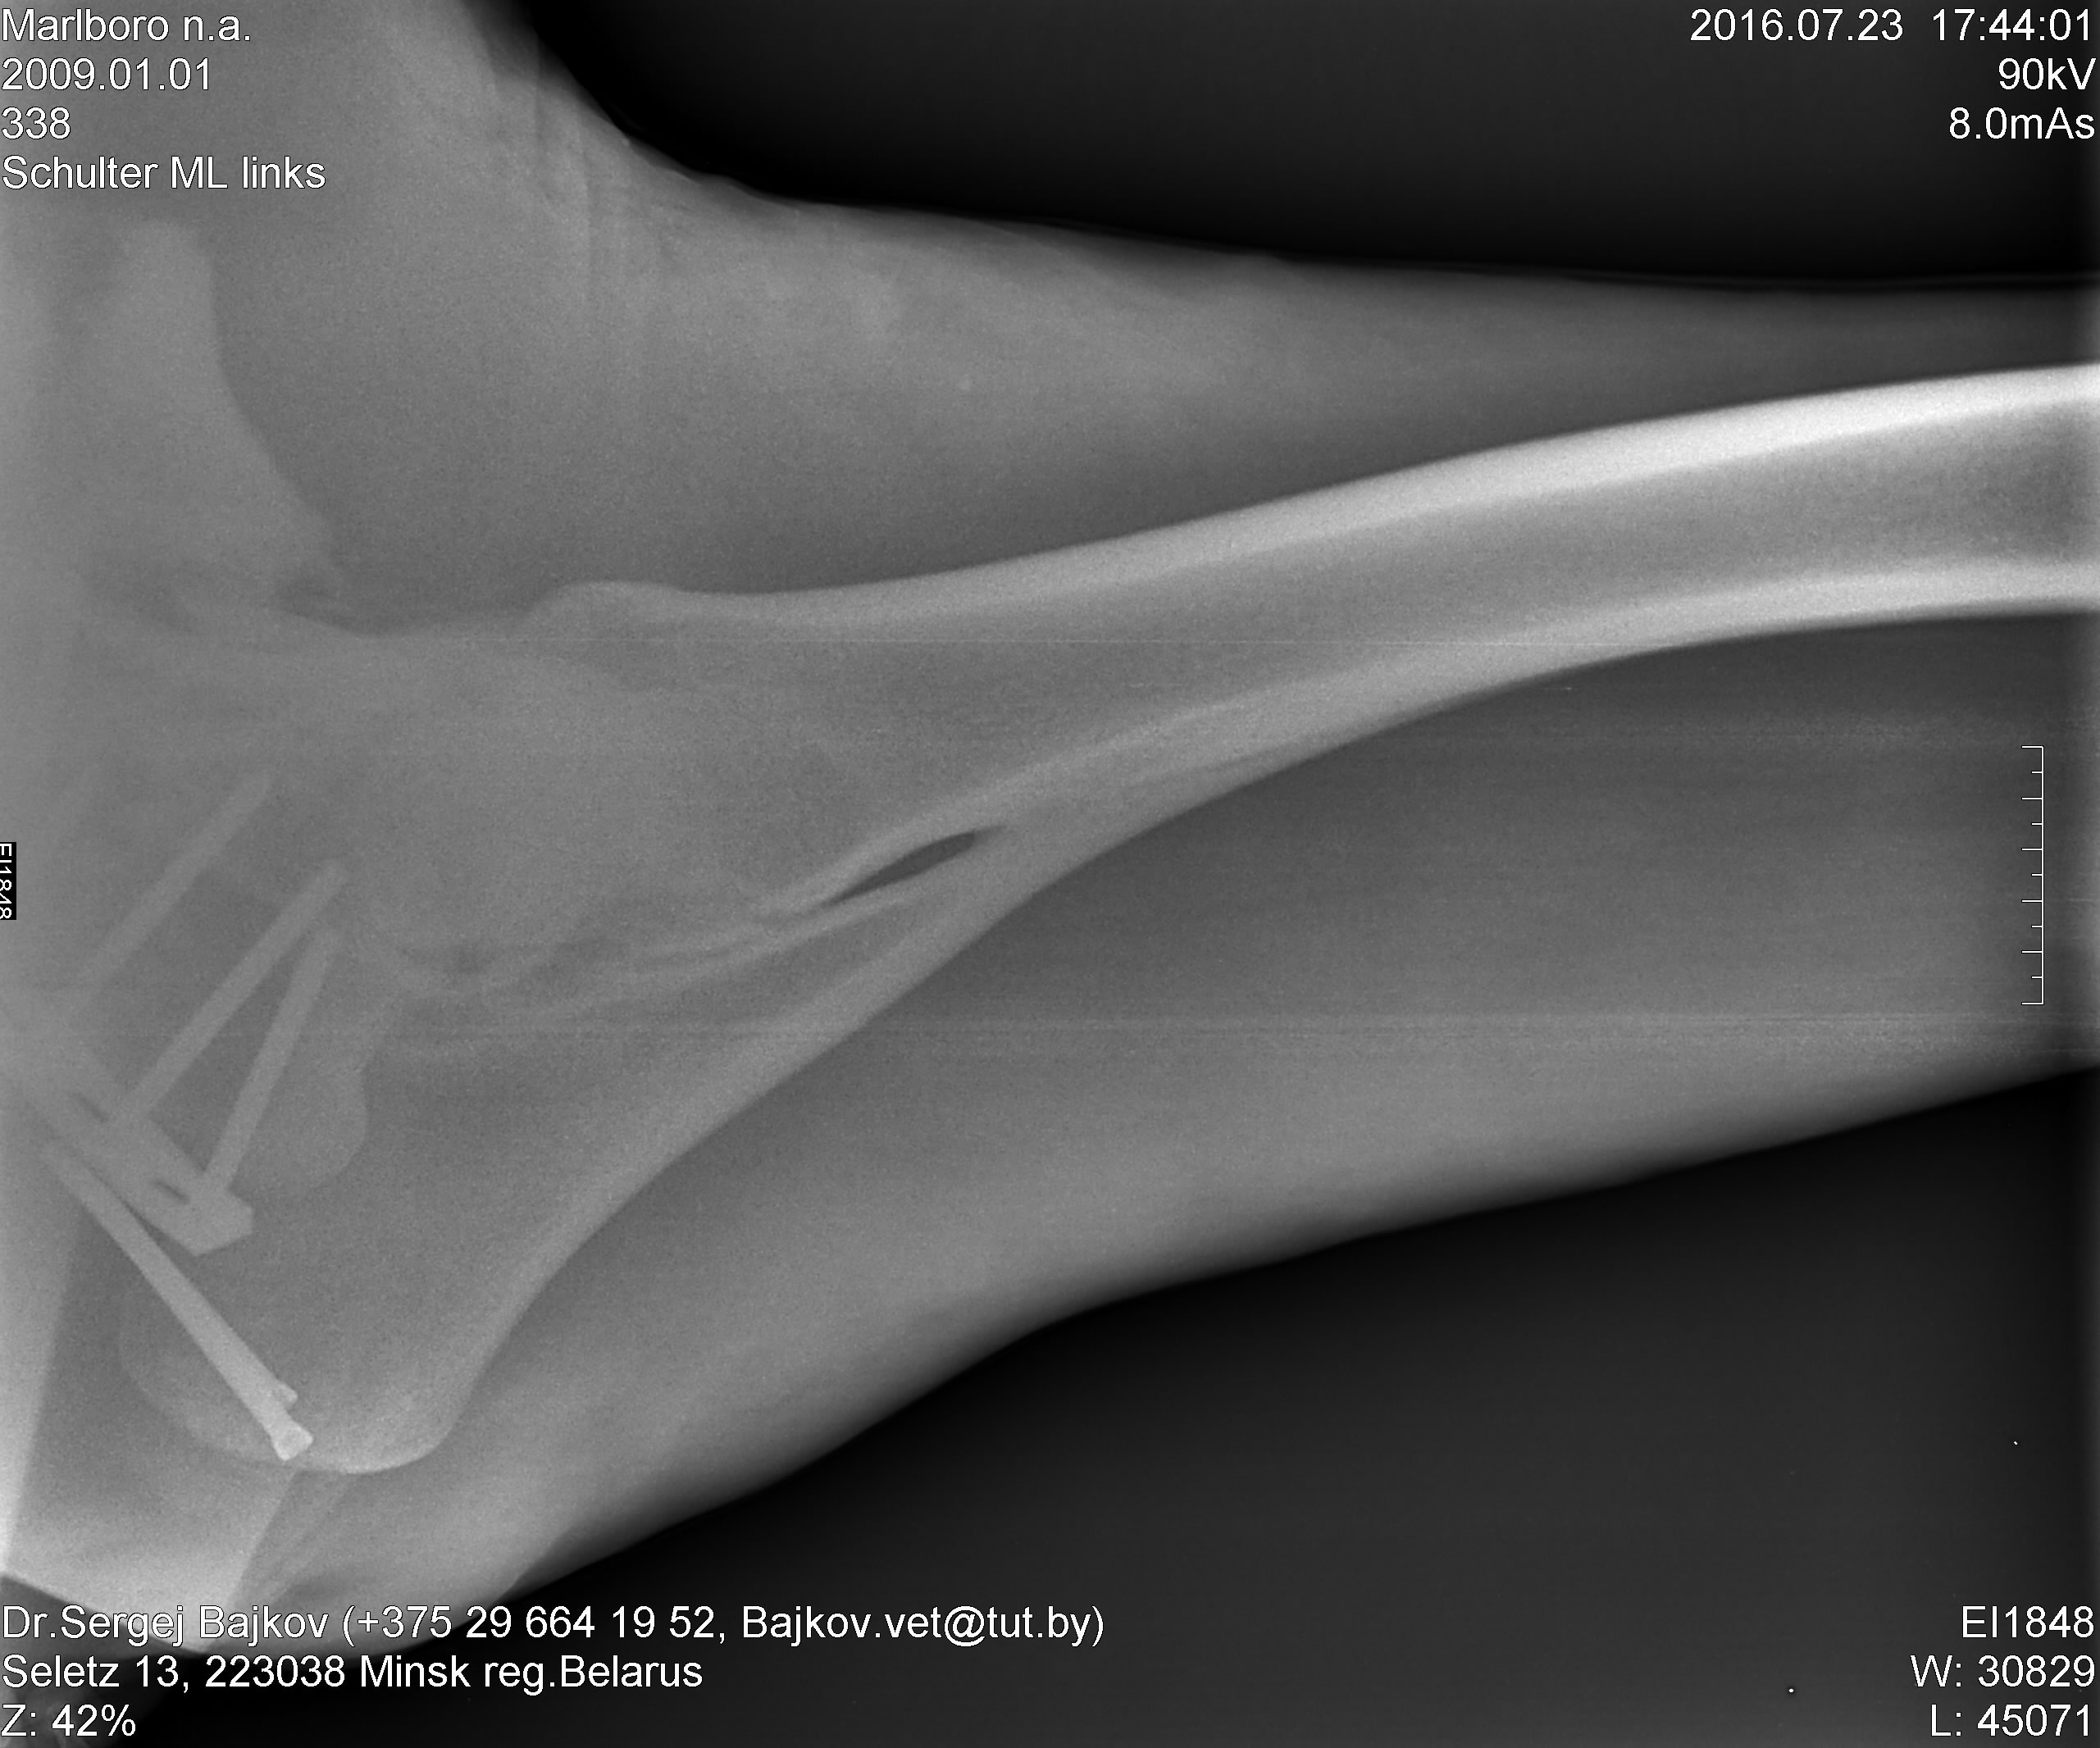

Наши снимки. К сожалению, снять получилось только нижний кусочек.

Докуда удалось достать -- все хорошо и по мнению оперировавшего хирурга, и по мнению Наташи-Кайхе.

Чуть позже выложу их комментарии.